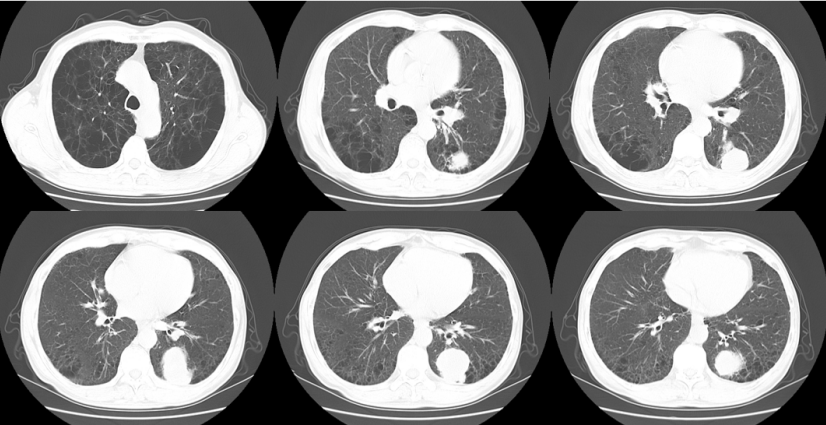

胸部增强CT(2023-11-18)

左肺下叶后基底段见肿块,大小约3.5 cm×4.8 cm,不均匀强化,考虑左肺下叶肺癌并左肺门淋巴结肿大,慢性支气管炎并双肺气肿(图1)

1  患者胸部CT(2023-11-18)

复查胸部CT(2024-02-16)

左肺下叶后基底段见肿块,大小约3.2 cm×4.7 cm,不均匀强化,双肺门淋巴结肿大较前片2024-01-16变化不明显,慢性支气管炎并感染,双肺气肿

2  复查胸部CT(2024-02-16)